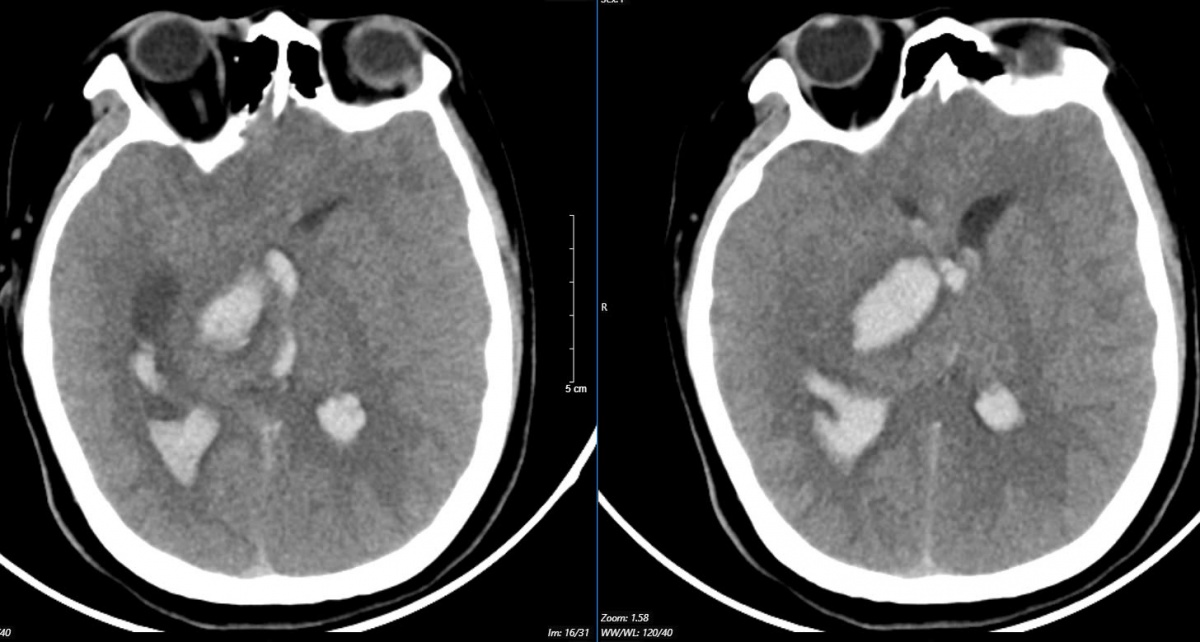

Hình ảnh chụp phim MSCT mạch não chảy máu não đồi thị - não thất do vỡ khối AVM (dị dạng thông động- tĩnh mạch não) bệnh nhân 15 tuổi. (Ảnh: BVBM CC)

Cụ thể, một bệnh nhân 15 tuổi đến viện vì đột ngột đau đầu dữ dội. Bệnh nhân nhanh chóng rơi vào tình trạng hôn mê. Bệnh viện tuyến dưới tiếp nhận chẩn đoán bệnh nhi bị chảy máu não, lập tức được đặt ống nội khí quản thở máy và nhanh chóng chuyển ngay đến Bệnh viện Bạch Mai.

Theo đó, bệnh nhân khi vào Trung tâm Đột quỵ, Bệnh viện Bạch Mai trong tình trạng ý thức hôn mê sâu, Glasgow 5 điểm, thở máy, giãn đồng tử bên phải. Kết quả chụp lại phim MSCT mạch não cho thấy chảy máu não đồi thị - não thất do vỡ khối AVM (dị dạng thông động - tĩnh mạch não), biến chứng giãn não thất cấp, rối loạn thân nhiệt, sốt cao liên tục 39 - 40 độ C. Khối dị dạng mạch não tuy không quá lớn nhưng ở vị trí cực kỳ nguy hiểm.